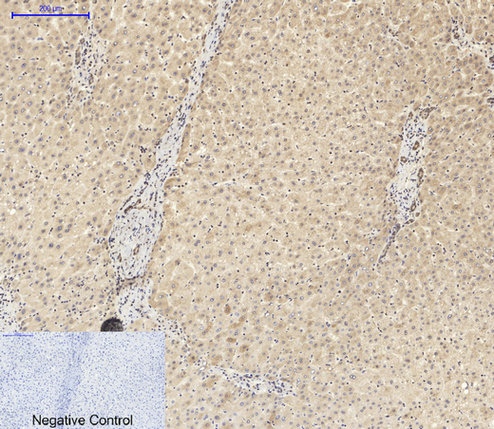

Immunohistochemical analysis of paraffin-embedded Human-liver tissue. 1,ASC Polyclonal Antibody was diluted at 1:200(4°C,overnight). 2, Sodium citrate pH 6.0 was used for antibody retrieval(>98°C,20min). 3,Secondary antibody was diluted at 1:200(room tempeRature, 30min). Negative control was used by secondary antibody only.